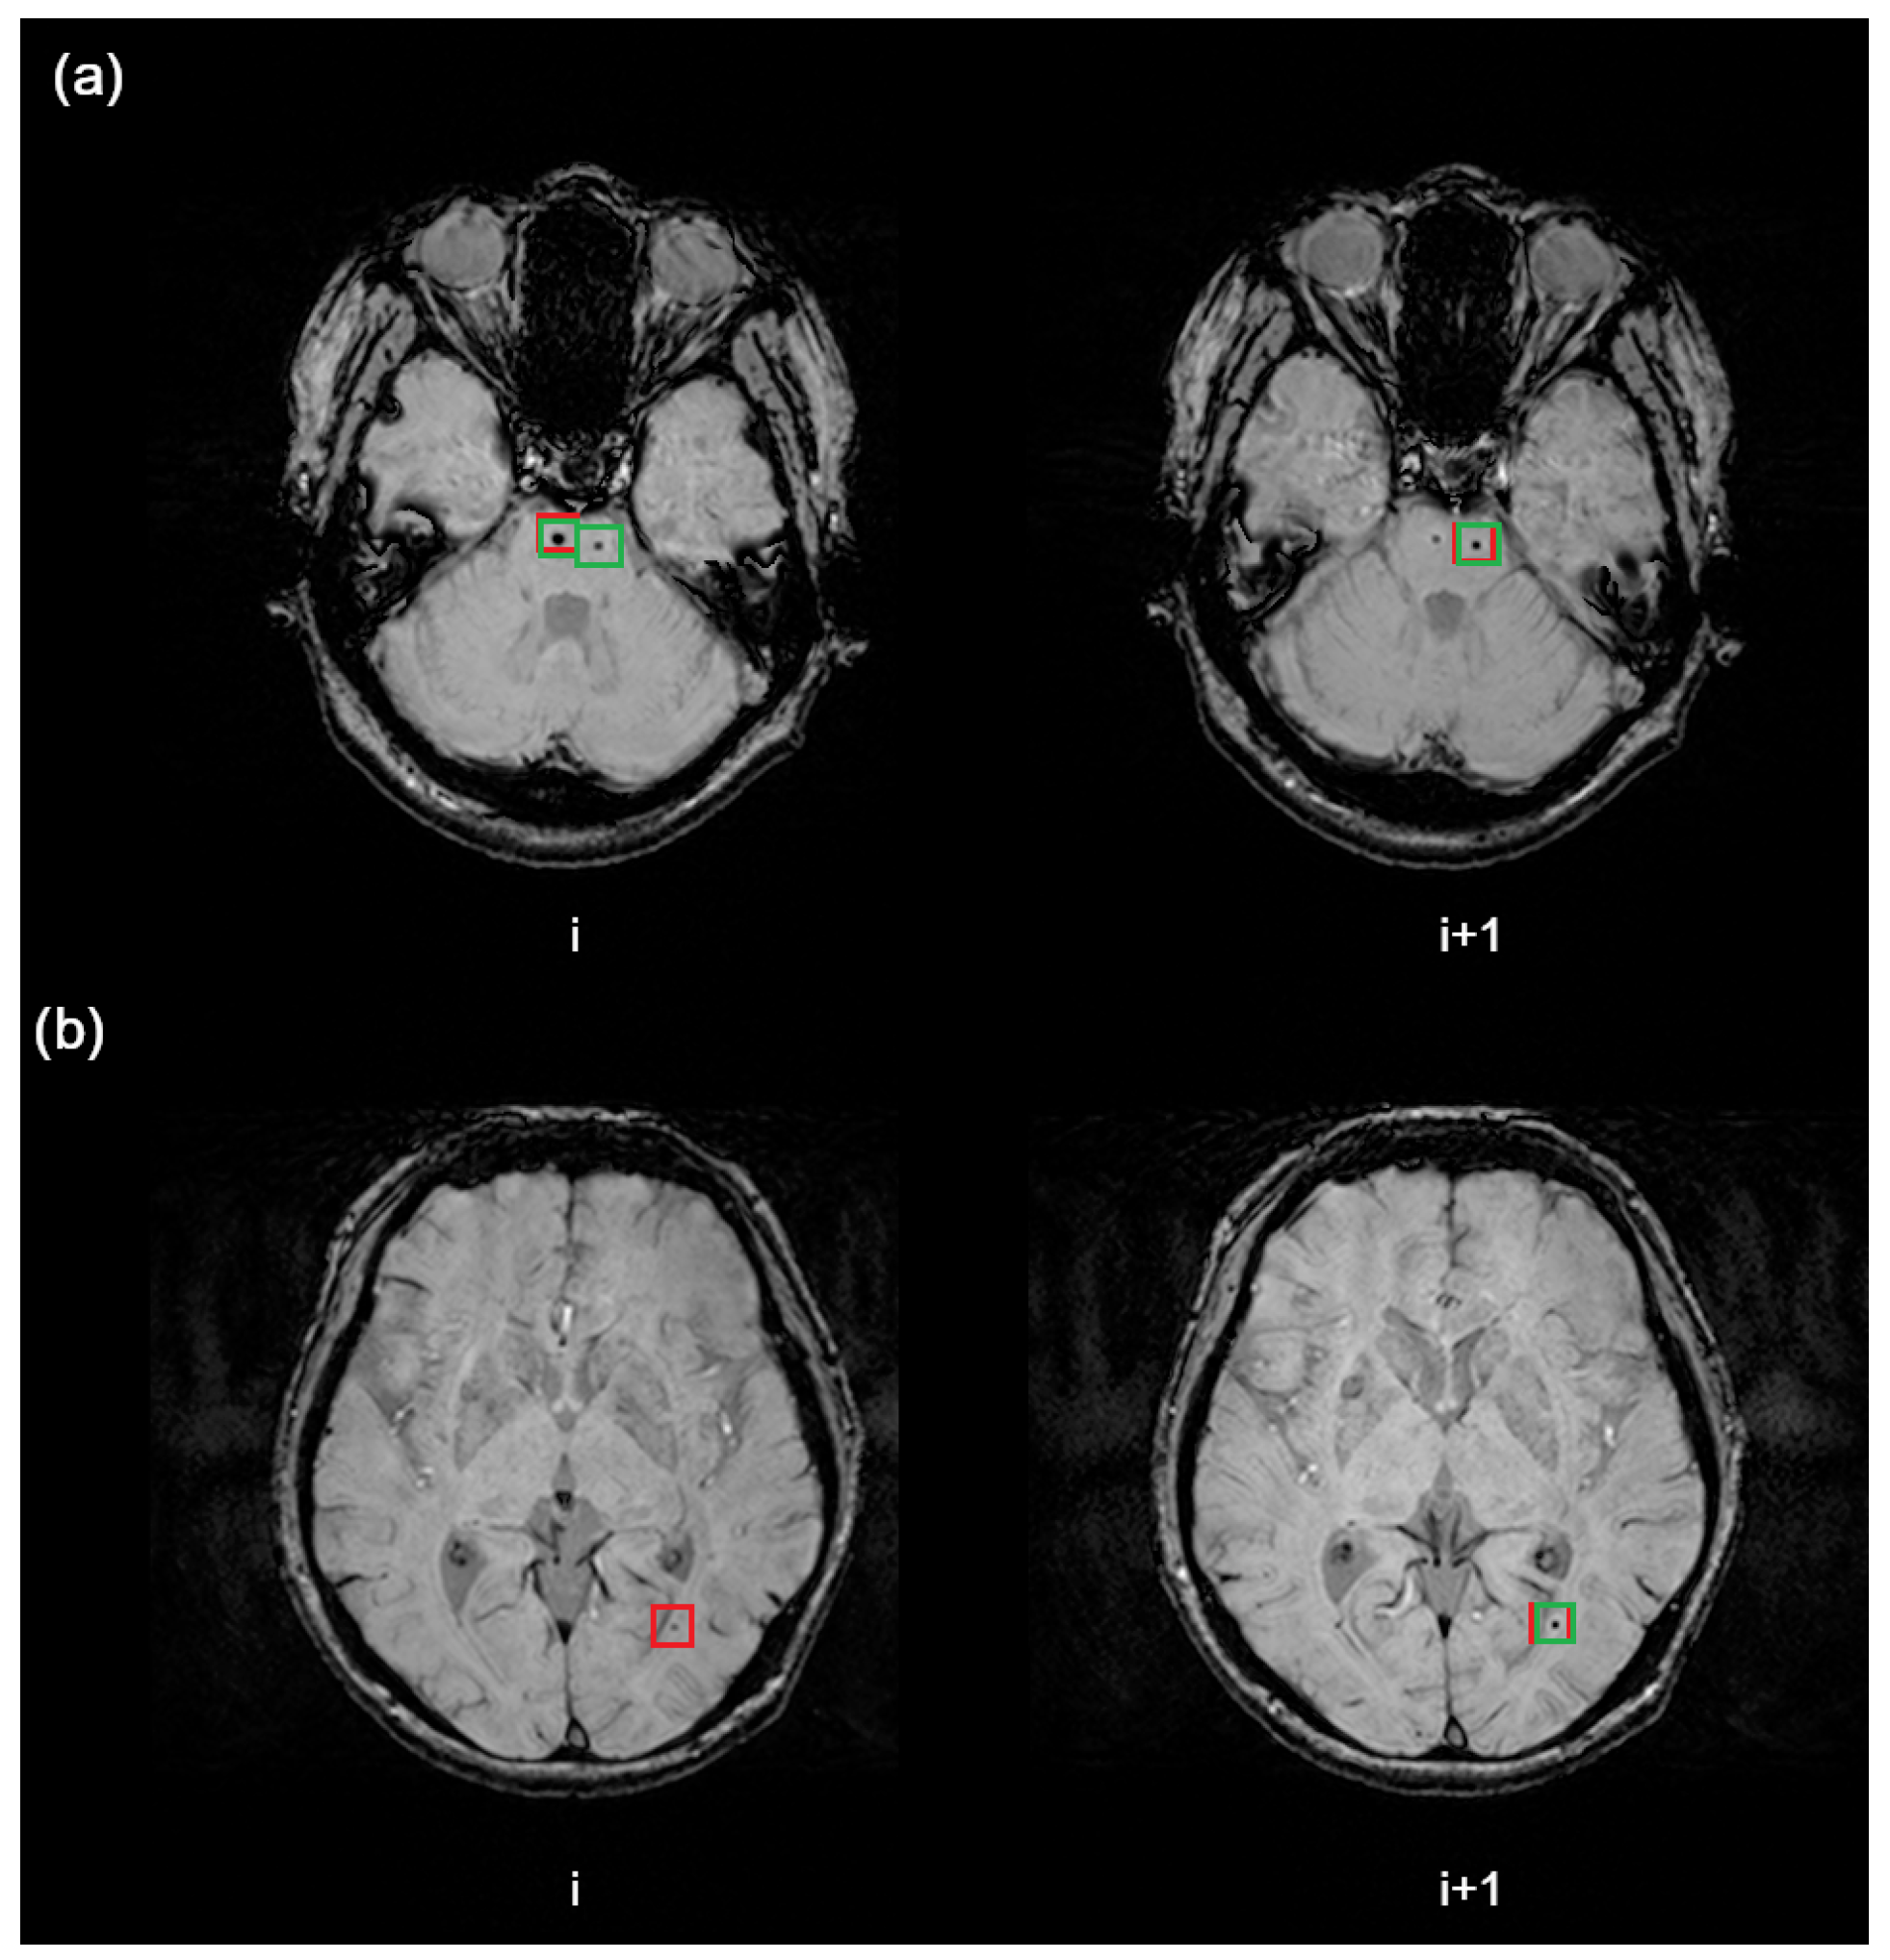

In Figure 5, we present examples of how the proposed algorithm works.

In the first case, the same microbleed was found in two adjacent slices (see case (a) in Figure 5). Even if there was a single label in one slice, we should not treat the other prediction as a false positive, since it is actually a true positive. Therefore, in the verification of false positives, we inspect if the prediction is already in ground truth CMB from adjacent slices. If yes, we mark a prediction as correct. Only if we do not find any ground truth CMB matching a prediction, we add it to False Positive.

Another case is when a ground truth CMB was not detected (see case (b) in Figure 5). However, it was verified that it was detected on the next slice. Therefore, it was added to the True Positive candidates. After inspection, if it is not duplicated, it was marked as True Positive, as this microbleed was actually detected in the adjacent slice.

This approach prevails, because it lets us evaluate the system in terms of the whole MR image, not only a single slice.

Figure 5. Two example cases presenting the application of predictions post-processing stage. The (a) example represents verification of false-positive prediction and (b) example represents verification of ground truth CMB detection.